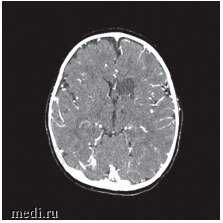

Появление неврологической симптоматики в сочетании с воспалительными изменениями в анализах крови послужили показанием к проведению компьютерной томографии (КТ) головного мозга, на которой визуализированы ишемические изменения вещества головного мозга левой лобной и затылочной доли с очагами пониженной плотности до 2 см в диаметре, не изменяющимися при введении контрастного вещества, что характерно для течения энцефалита (рис. 2). Ребенку была выполнена спинномозговая пункция.

Рис. 2. КТ головного мозга: ишемические изменения вещества головного мозга левой лобной и затылочной долей, что, вероятнее всего, является проявлением энцефалита